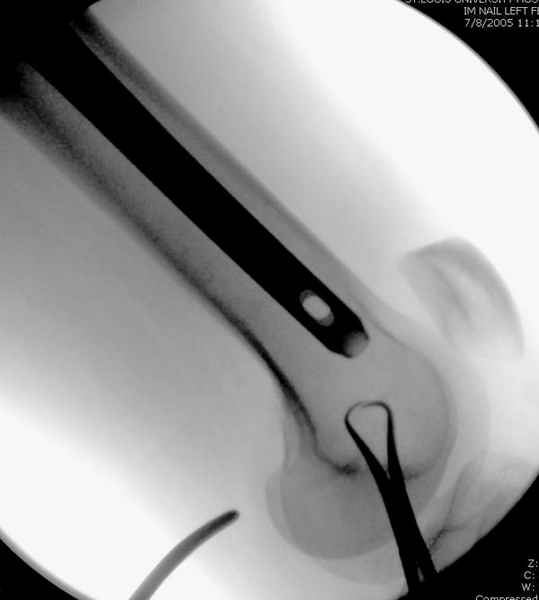

Второй случай тоже репозиция из малого доступа, больному 19 лет, множественные огнестрельные повреждениия конечностей, живота и черепа, правая конечность холодная, без пульсации. Ортопедический диагноз: огнестрельный перелом правого бедра. При срочной ангиографии повреждения сосудов не подтвердилось, конечность из-за ургентности состояния больного зафиксирована временным наружным фиксатором и больной оставлен на операционном столе для срочной лапаротомии хирургической службой.

Больной долго оставался нестабильным, только на 14 день удалось заменить на антеградный интромедуллярный штифт TFN (trochanteric femoral nail) SmithNephew. После неудачной попытки закрытой репозиции, несмотря на использование "joystick", проксимальный стержень от

наружного фиксатора, (перелом начал срастаться) репозицию провели из малого доступа, затем остальные этапы операции.

Случай был представлен из-за того, что больного оперировали после наружной фиксации и был риск инфекцирования через места проведения стержней (на снимках), прошло больше 3 месяцев, выписан из амбулаторной службы из-за отсутсвия надобности дальнейшего наблюдения.